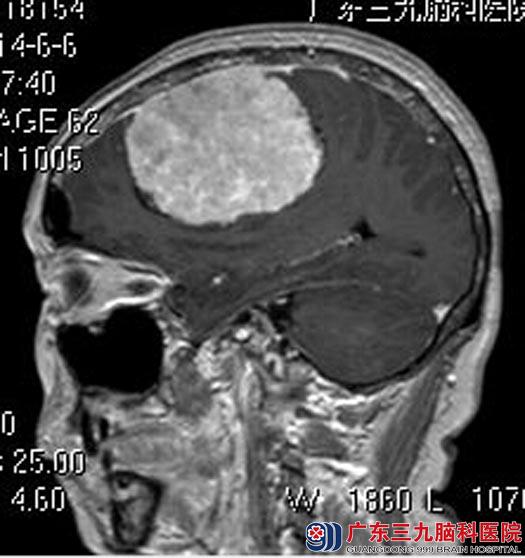

广东三九脑科医院进一步MR检查提示:右侧额部大脑凸面示一较大的团块状占位性病变,大小约7.33cm×5.65cm×5.63cm。

为最大程度切除肿瘤,术前完善导航计划,由综合神经外科鲁明主任主刀,在全麻下行右侧额叶脑膜瘤切除术,术中再次导航定位,显微镜下见肿瘤与脑膜粘连,血供丰富,在镜下将肿瘤全切。